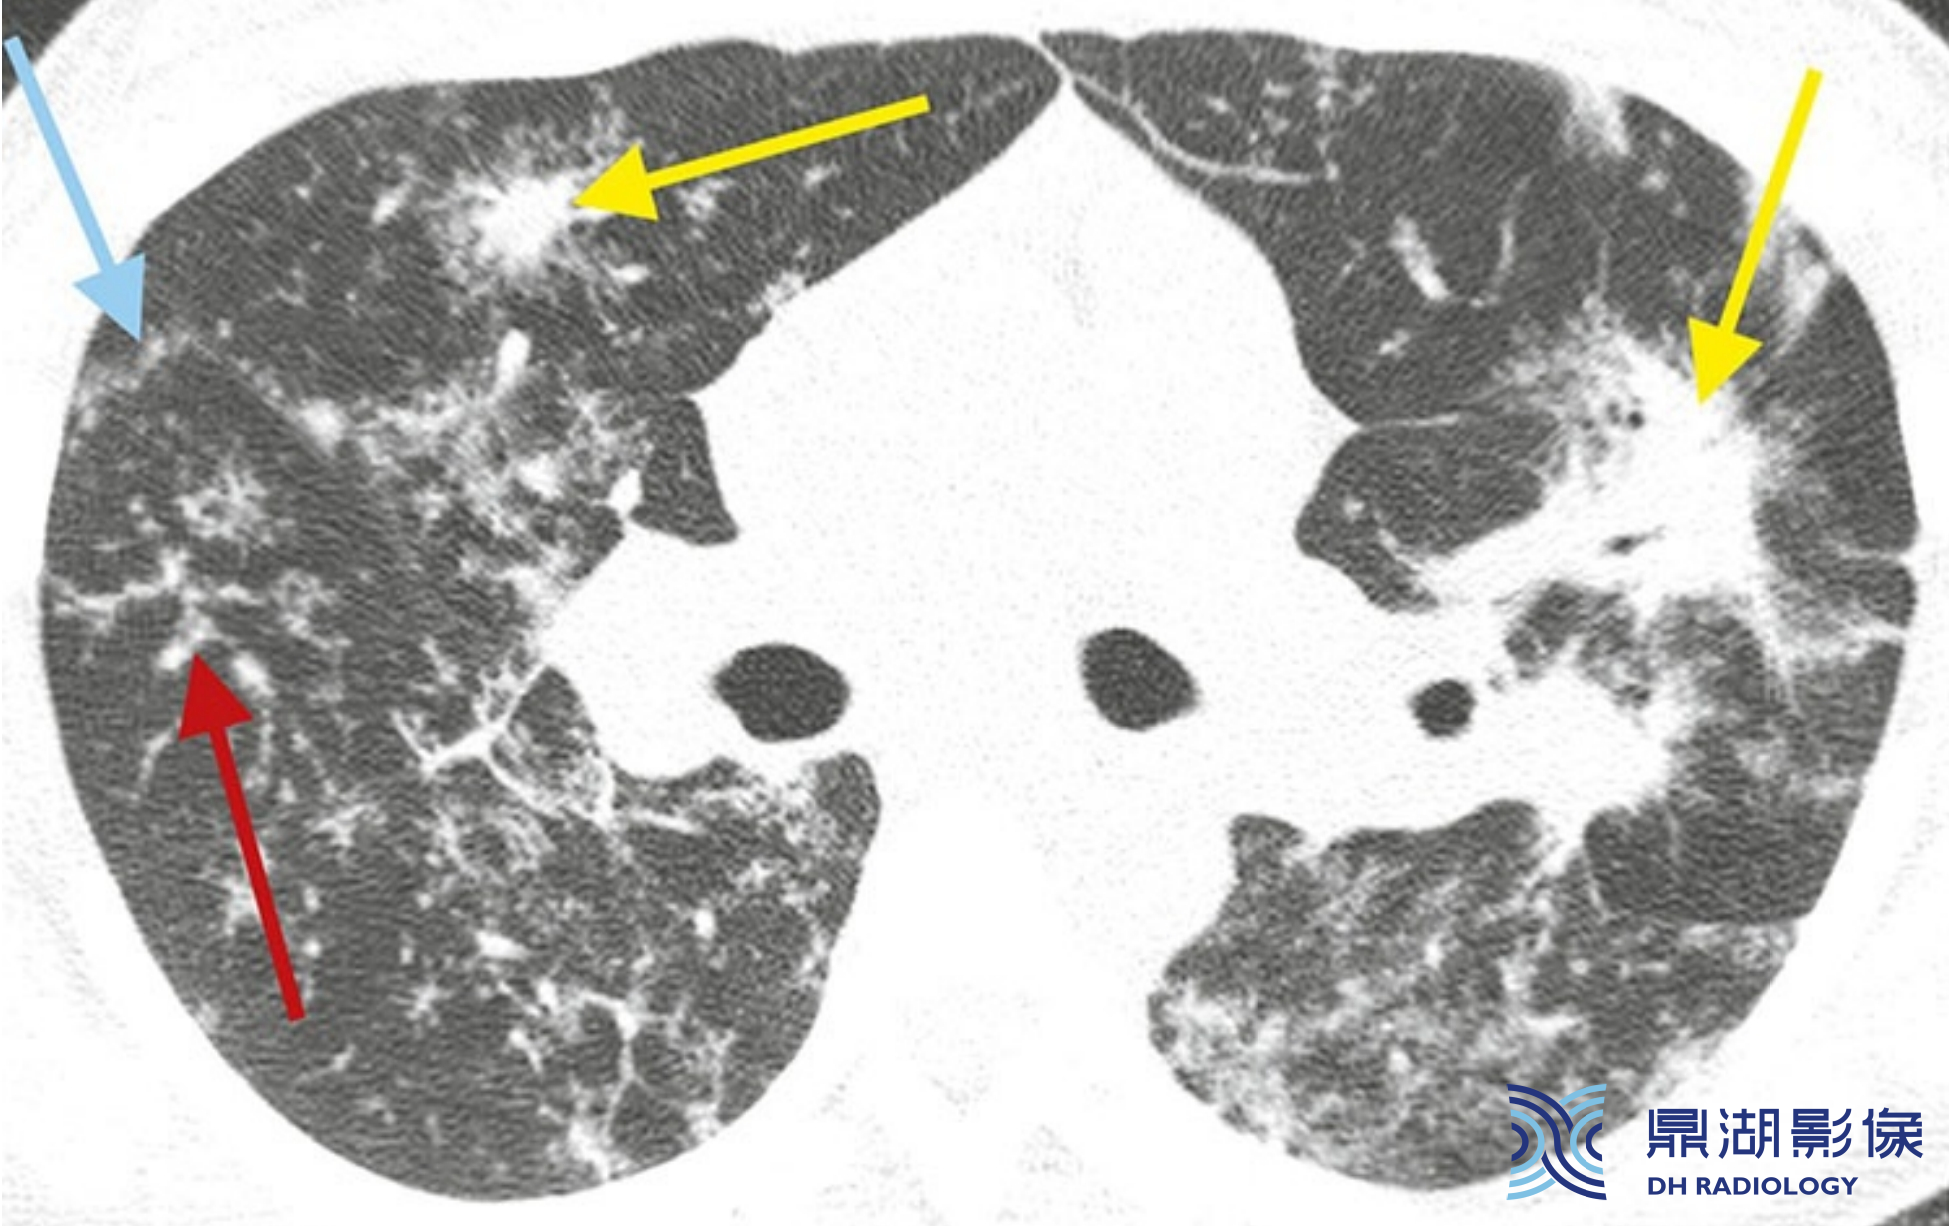

a6e40d7ee5c68dbaf183e07ee5edee07.jpg

结节病的典型表现。

A至C广泛累及肺部的结节病患者,HRCT可见簇状和团块样结节,包绕肺门的动脉、支气管及支气管血管周围间质(红箭,B), 分布于外周支气管血管周围(红箭,A和C) 、肺外周及与叶间裂相邻的胸膜下间质(蓝箭)。